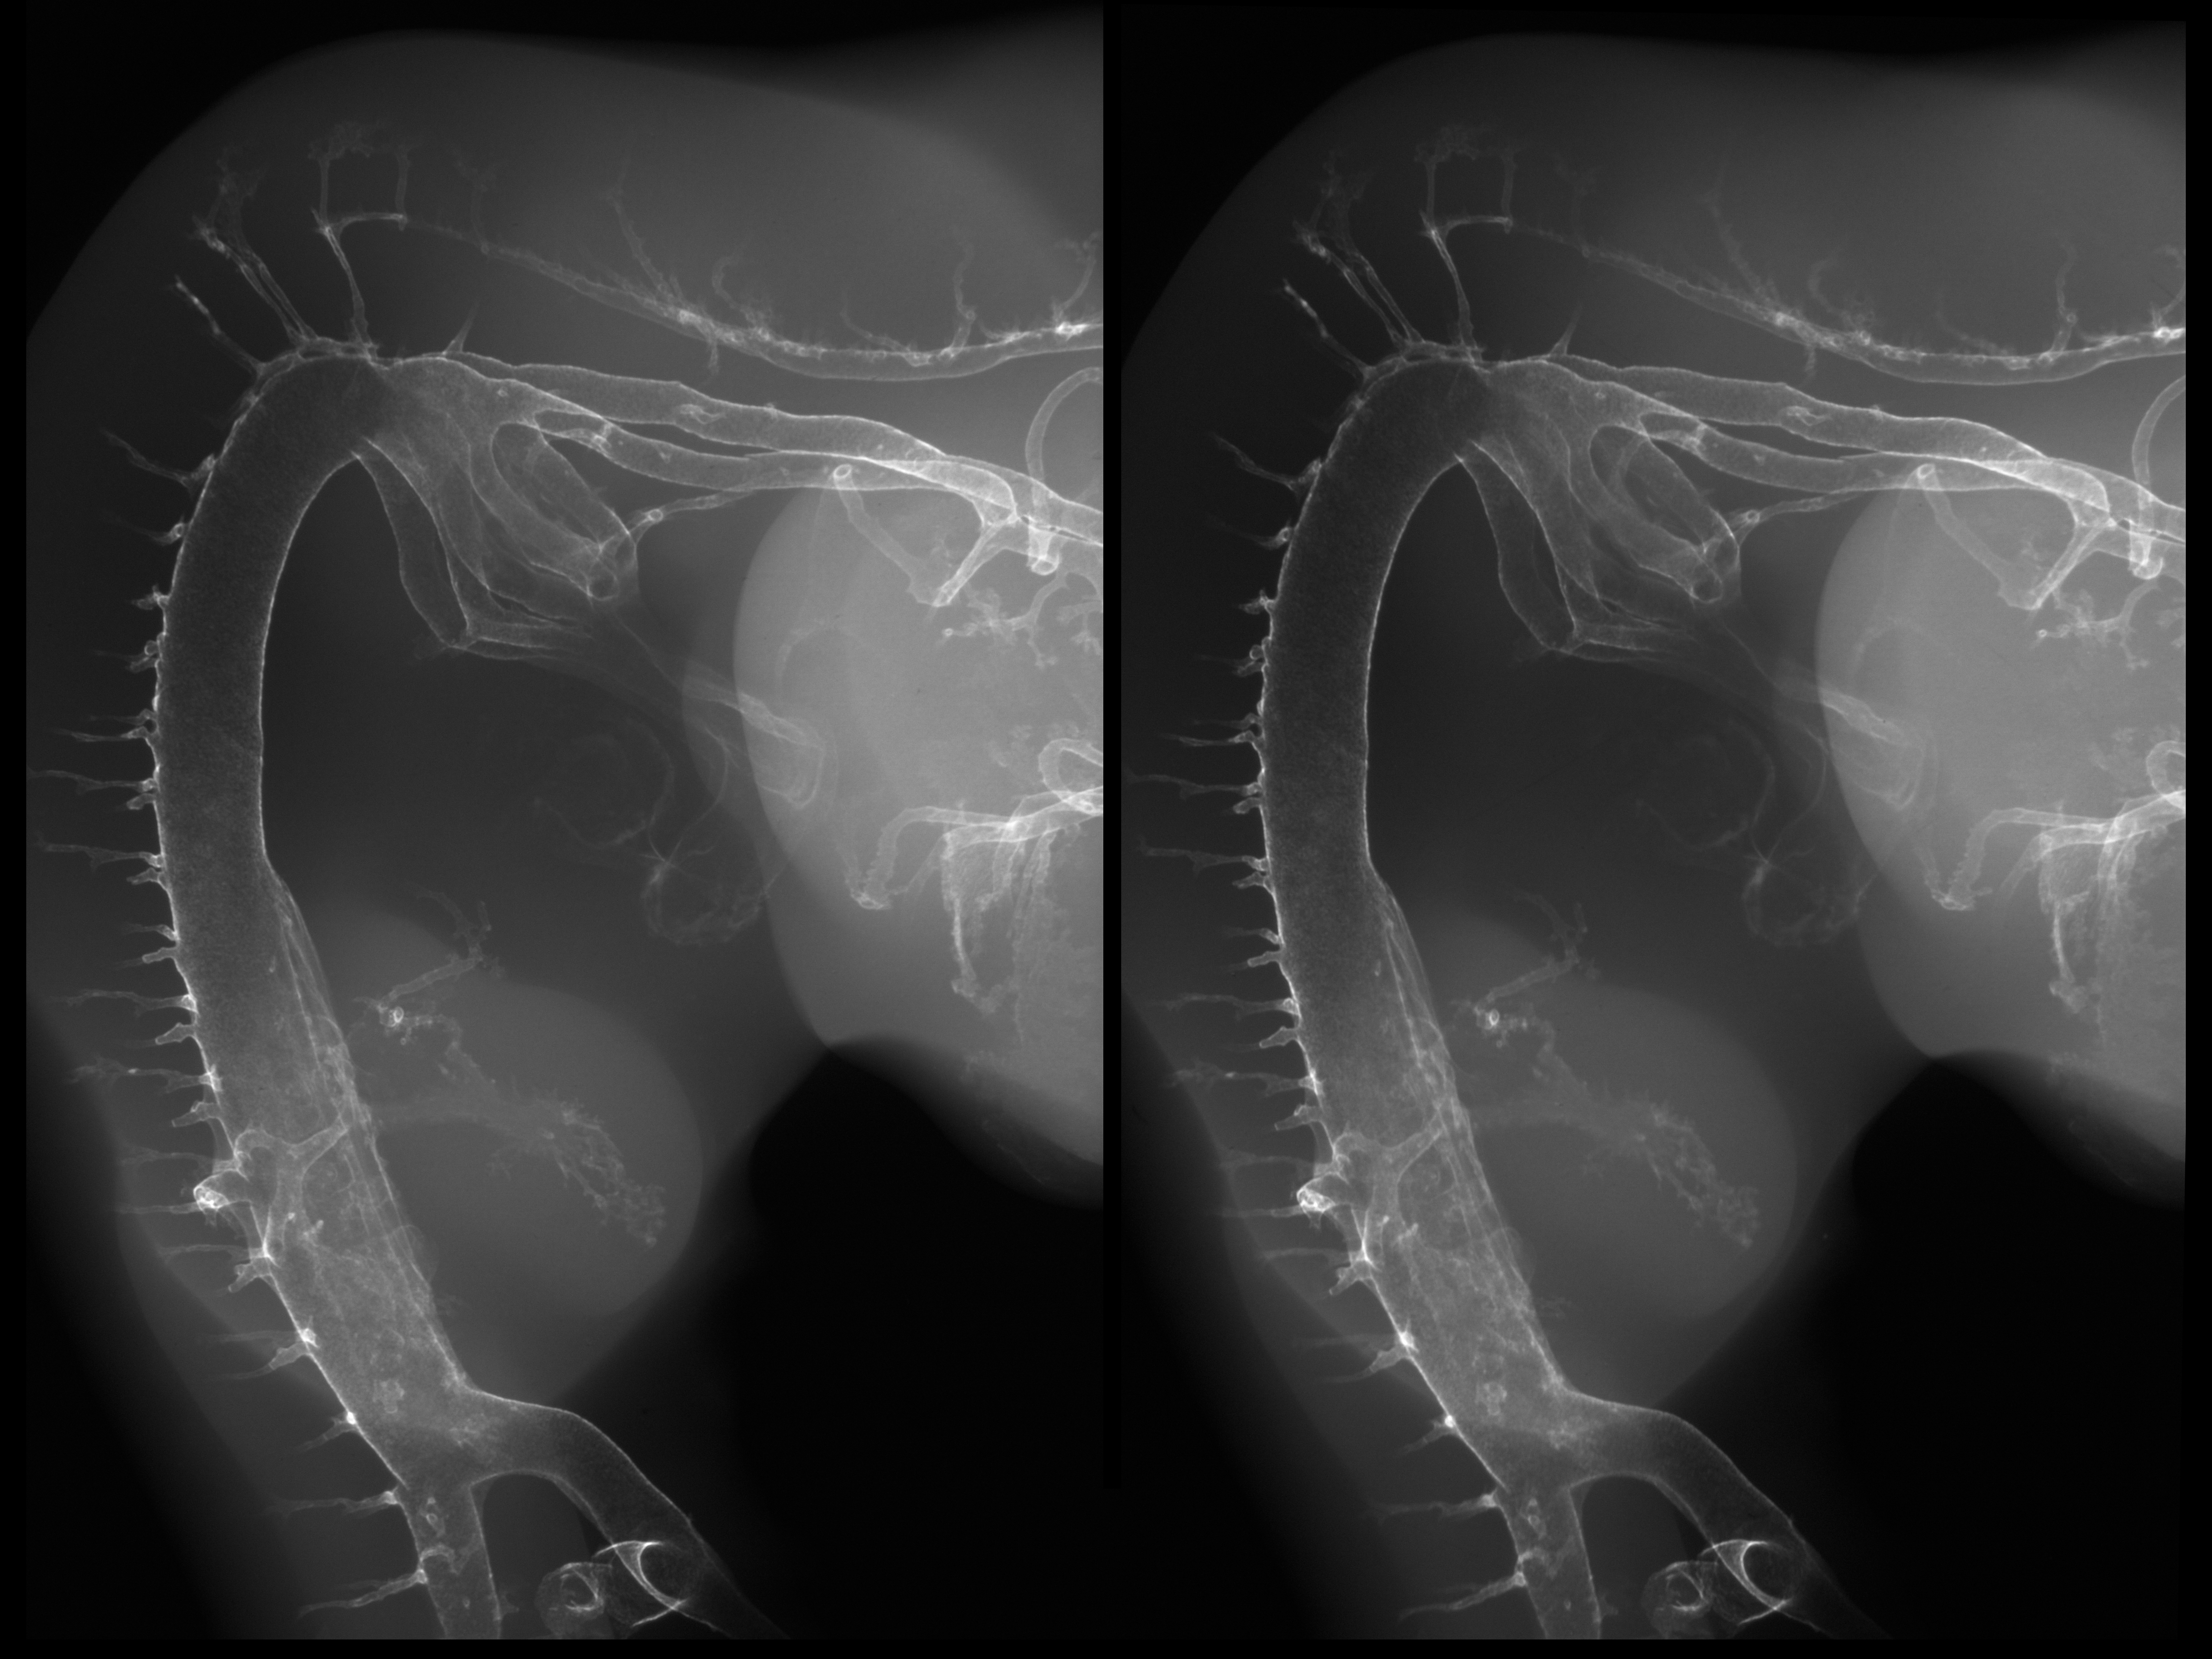

Chick Embryo Microangiography

Hamburger-Hamilton (HH) Stage 25 (approx. 4.5 - 5 days)

Stereo X-Ray Micrographs